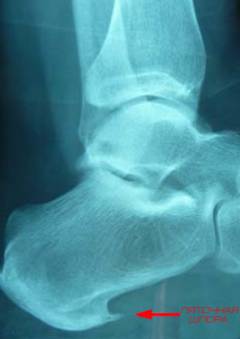

Для выявления остеофитов стопы чаще всего используется рентгенография. На рентгеновском снимке пяточная шпора может иметь шиповидную, клиновидную или шиловидную форму, отходящую от пяточного бугра. Рентгенография позволяет обнаружить эту патологию в большинстве случаев, поэтому другие методы, такие как компьютерная томография и магнитно-резонансная томография, назначаются только при необходимости получения информации о близлежащих тканях.

Остеофиты стопы чаще всего образуются на пяточной кости из-за воспалительно-дегенеративных изменений подошвенной фасции, что приводит к плантарному фасцииту. Предрасполагающие факторы — чрезмерные нагрузки и травмы пяточной кости.

Диагноз ставится на основании жалоб и объективного осмотра, подтверждается инструментальными методами, чаще всего рентгенографией.

Рентгенография позволяет выявить пяточную шпору, которая может иметь различные формы. Другие методы, такие как компьютерная томография и магнитно-резонансная томография, используются реже.